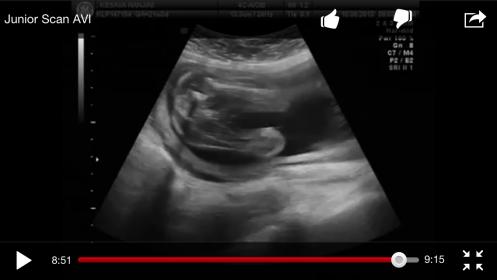

Junior Scan AVI - YouTube

Congrats on your beautiful baby! I am not an u/s tech and may have missed something but there is a quick potty shot @ 8:51 in the video that looks like a girl. Did you not ask to know the sex? If so and you want to know now I'm sure the tech looked and it got jotted down. You could call them. :)

My guess is boy!!! You get a quick glimpse between 1:31 and 1:32 it's really fast but looks clear to me. But I'm no tech

Those definitely look like boy bits! Here is the screen shot I got @8:51. So maybe the 3 lines I'm seeing is the umbilical cord? This shot I got while watching on my phone and was able to get it to stop frame by frame easier than when watching it on my computer. Attachment 13096

I see those 3 lines but its still pretty fuzzy and unclear. I'm still thinking boy!